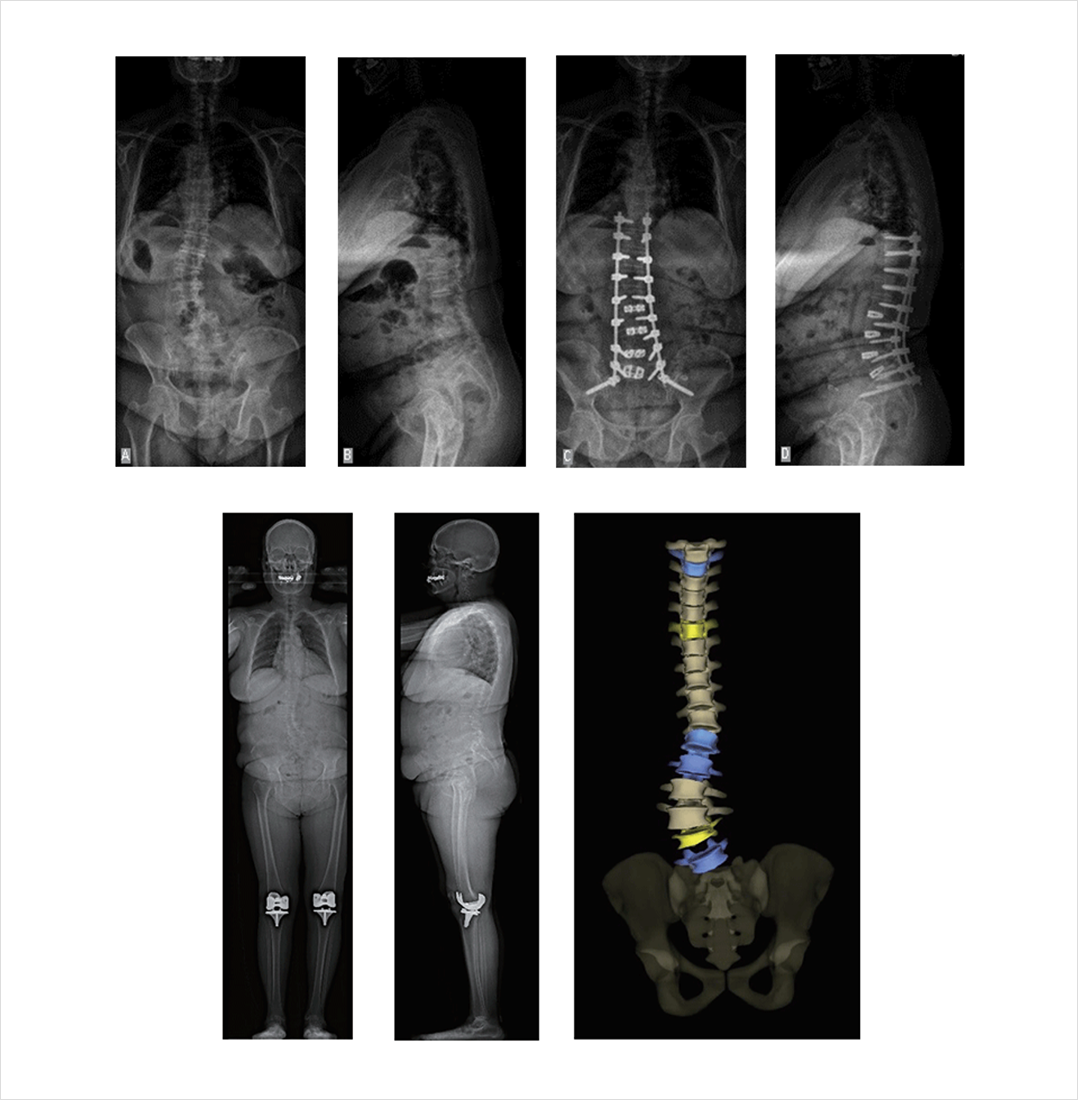

전신 척추 전후면 및 측면 영상(Whole spine AP and Lateral X ray)을 통해 척추의 균형 상태를 파악해야 합니다.

배 쪽으로 휘어 있어야 할 요추부 전만곡이 거꾸로 등쪽으로 휘어 허리가 굽게 되고, 이를 보상하기 위해 흉추부 후만곡은 반대 방향인 가슴 쪽으로 휘는 상태가 확인됩니다.

또한 처 음에는 똑바로 서 있다가 시간이 지남에 따라 근육이 피로해지면서 시간대별로 찍어(초기, 5분, 10분 간격) 어떤 부위에서 시상면 변형이 심하게 일어나는지 관찰할 수 있습니다. 최근에는 저선량 체중부하 X ray 검사인 EOS 검사를 이용하기도 합니다.